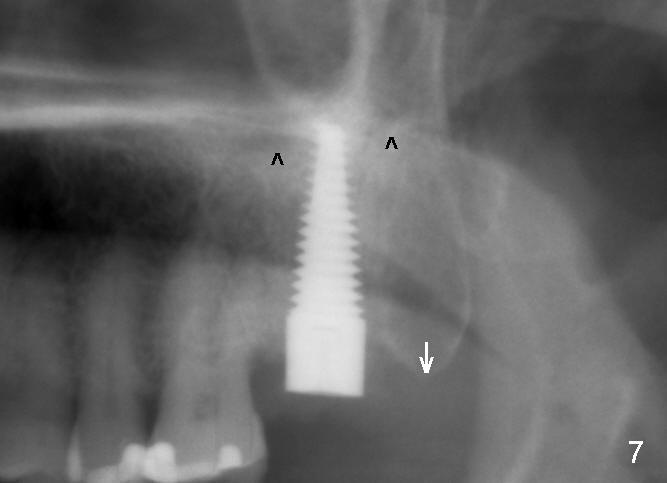

A 57-year-old lady presents for abscess buccal to the tooth #15 (Fig.1 A). Mesial and distal to the occlusal composite (Fig.2 C) is a crack line. In addition to long furcated roots, the upper border of the bone is not shown in this preop PA (arrow). Fig.3 is taken to show a thin septum surrounded by the mesiobuccal (MB), distobuccal (DB) and palatal (P) sockets (Fig.3). Osteotomy is initiated in the septum by 1.2 and 1.5 mm pilot drills, followed by 2,3,4 mm rounded tapered osteotomy at the depth of 17 mm. Nose blowing test is carried out after each step with negative result. Stability is achieved when a 4.5 mm tap is inserted at 17 mm, but the upper end of the tap is not visible (Fig.4,5). When a 5 mm tap is placed, stability is decreased, probably because the coronal end of the septum starts to break down (due to expansion). To re-gain stability, the 5 mm tap needs to go deeper. A 6 mm tap also achieves satisfactory stability at 20 mm. When the tap is removed, there is no air leakage. A 6x20 mm implant is placed with insertion torque > 60 Ncm; the upper end of the implant is still out of view in PA (Fig.6). Another problem is that the implant needs to go deeper to obtain sufficient occlusal clearance. The lower first molars and the 2nd premolars are missing. A panoramic X-ray has to be taken to show the apical end of the implant: ~ 3 mm into the sinus (Fig.7 ^). The maxillary tuberosity appears to grow downward (arrow). In other word, the tooth #15 appears to have been intruded due to overloading.